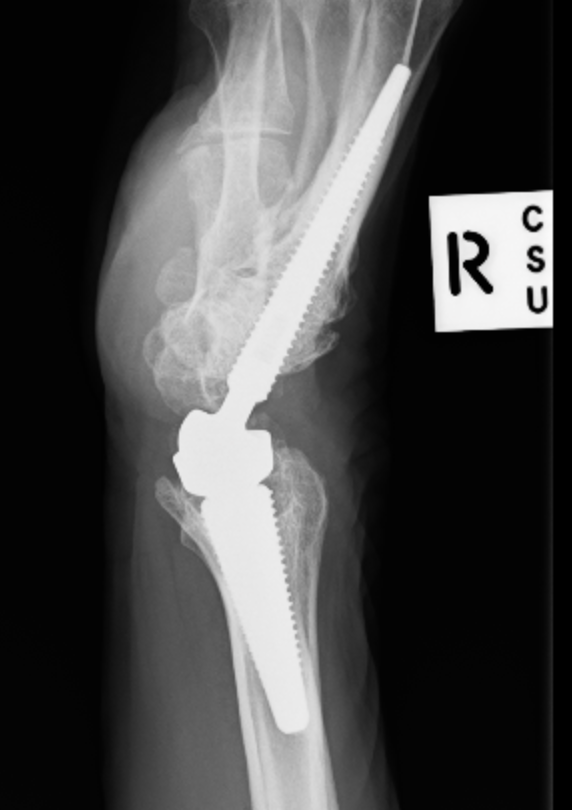

Galeazzi fractures

Fracture of the radial shaft with disruption to the distal radio-ulna joint (DRUJ)